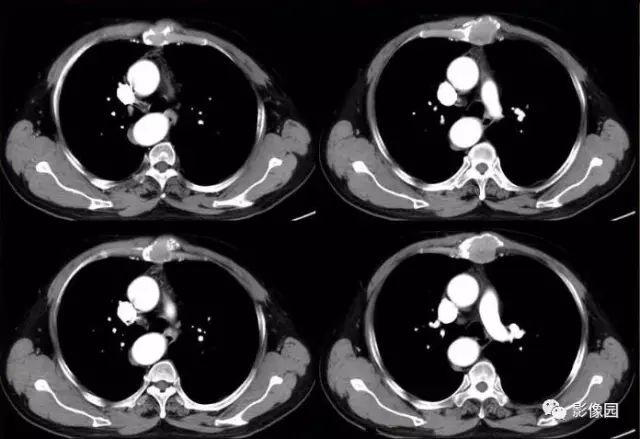

肚肚丫头: 胸骨体局部呈膨胀性骨质吸收破坏,内呈软组织密度影,可见点状钙化,增强扫描呈轻度强化,周围软组织略肿胀。考虑:1.骨巨细胞瘤;2.浆细胞瘤;3.嗜酸性肉芽肿

CT表现:特征性穿凿状、鼠咬状及蜂窝状骨破坏,边缘清楚,骨质疏松,病理性骨折及软组织肿块等表现,骨质硬化及骨膜反应少见。

骨破坏区完全为软组织取代,骨质膨胀,边界清楚,常突破骨皮质形成软组织肿块。增强扫描可见病灶轻中度强化,一般于静脉期达峰值。